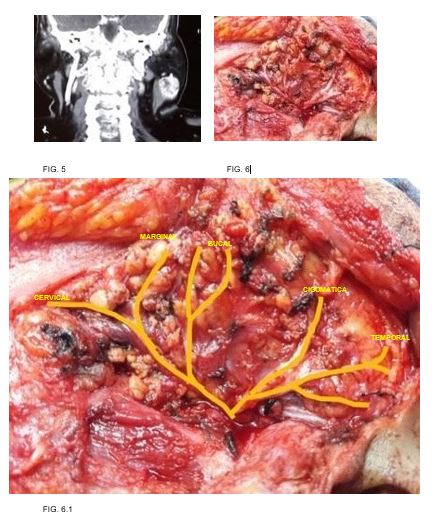

Caso 1: Masculino 49 años de edad, antecedente de tabaquismo e hipertensión, tumor parotídeo derecho de 5x3.5x2.5 pétrea. fue sometido a parotidectomía supraneural, resultando en melanoma maligno nodular con patrón sarcomatoide. (FIG. 1-2)

1

2

Caso 2: Femenino 40 años de edad, antecedente de hipertensión e hipotiroidismo, con tumor izquierdo 4 x 5 cm. fue sometido a parotidectomía supraneural, resultando en adenoma pleomorfo. (FIG. 3-4)

3

Caso 3: femenino 70 años de edad, antecedente de hipertensión, tabaquismo, diabetes mellitus y dislipidemia, con tumor parotídeo izquierdo de 6cm en su eje mayor, resultando en tumor de Warthin. (FIG. 5-6)

4